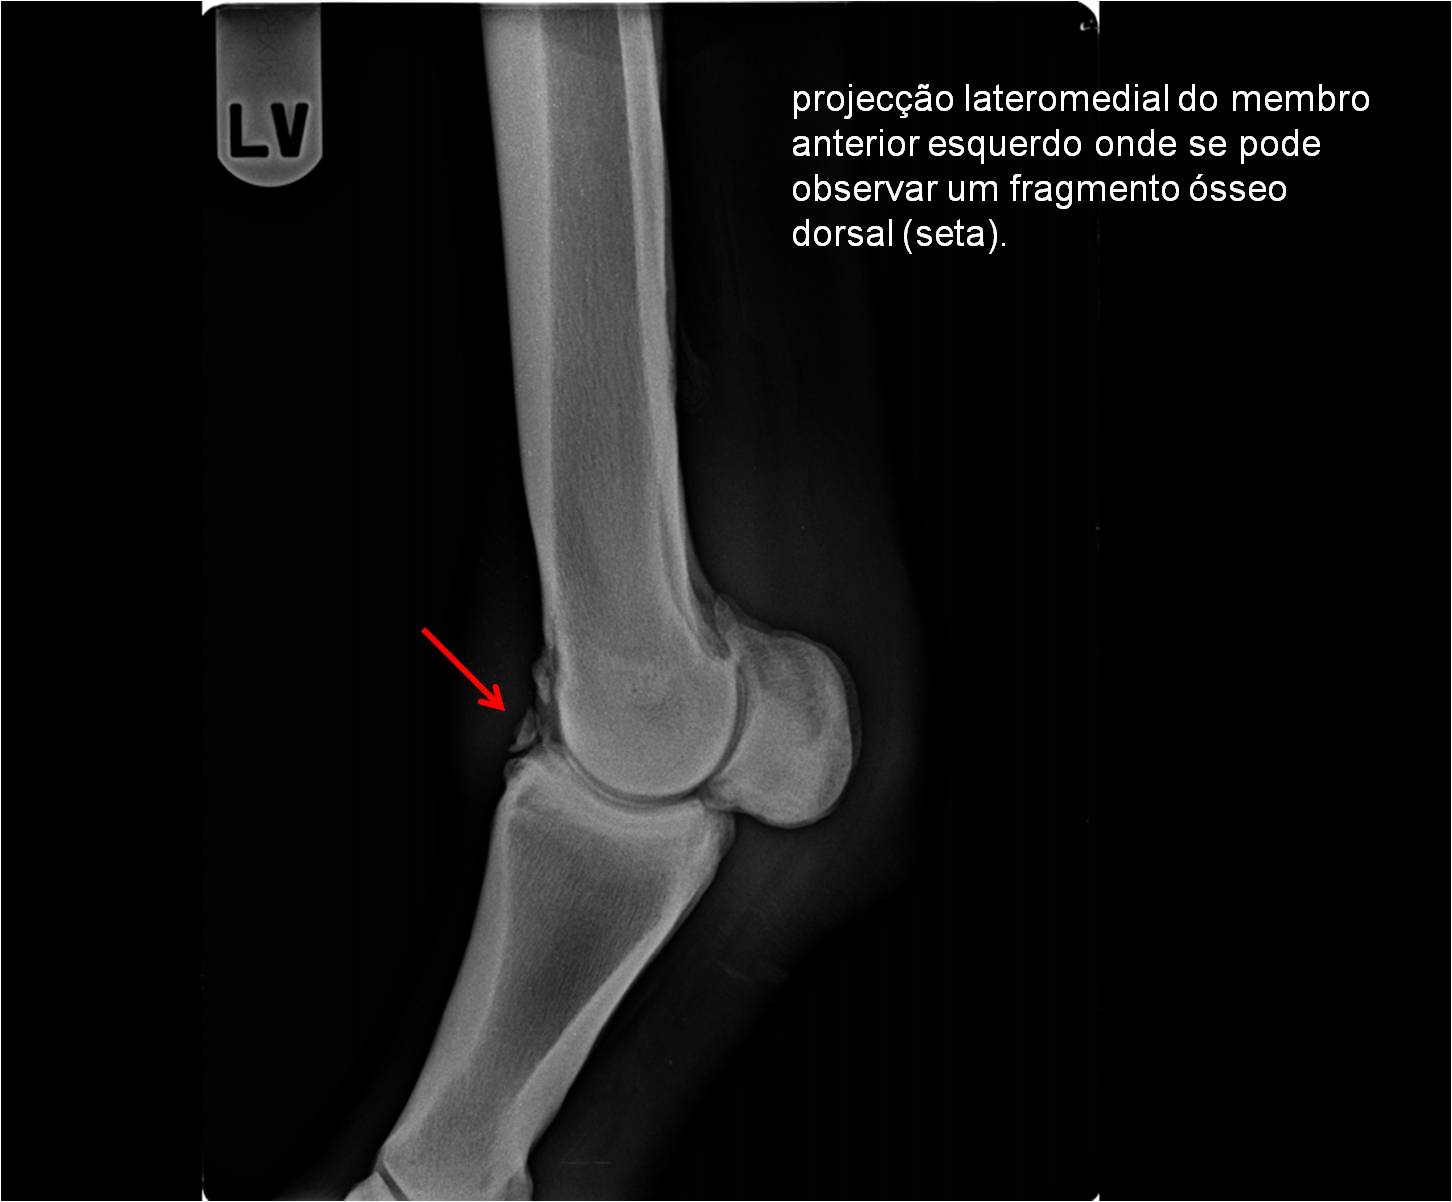

Publisher: Universidade de Évora

Abstract: O relatório de estágio encontra-se estruturado em três partes distintas. A primeira parte faz a caracterização das infraestruturas e funcionamento do Hospital Veterinário de Equinos de Lüsche, Oldenburg, Alemanha, assim como a análise casuística dos casos clínicos acompanhados durante os 6 meses de estágio. A segunda parte consiste de uma revisão bibliográfica sobre quistos do osso subcondral em equinos. Por fim, a terceira parte consta da apresentação e discussão de um caso clínico, nomeadamente o diagnóstico e acompanhamento imagiológico, por ressonância magnética, de um quisto subcondral na terceira falange num cavalo adulto; ### Abstract Equine Practice- Subcondral bone cyst of the third phalanx This internship report is divided in three parts. The first part characterizes the infrastructure and function of the Equine Hospital Lüsche, Oldenburg, Germany, as well as the casuistic of the clinical cases accompanied during the 6 month internship. The second part consists in a bibliographic review of cystic lesions of the subchondral bone in equines. The third part consists in a case report, the diagnostic and imagiological accompaniment, by use of magnetic resonance imaging, of a subchondral bone cyst in the distal phalanx of an adult equine.